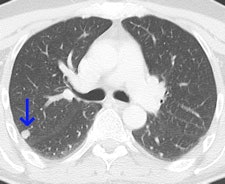

This 62-year-old melanoma patient has a 10-mm metastasis in the right upper lobe. The CT image (left) failed to show increased tracer uptake on the F-18 FDG PET image (right). All images courtesy of Dr. Marius Mayerhoefer.

The same patient as seen with the fused color-coded PET/CT image.F-18 FDG PET can help in the workup of pulmonary nodules because it reflects the tissue glucose metabolism, which is elevated in most malignant lung lesions. But mainly due to its limited spatial resolution, the sensitivity of PET for detecting pulmonary metastases is only moderate: In melanoma patients, it is between 57% and 70%, according to Mayerhoefer.

"CT can reliably detect even very small pulmonary nodules, owing to the high contrast between the nodules and the surrounding lung tissue, and thus has a higher sensitivity than PET for the detection of pulmonary melanoma metastases," he stated. "However, CT cannot reliably distinguish between benign and malignant lesions and is therefore less specific. The introduction of PET/CT has improved the situation in this regard."